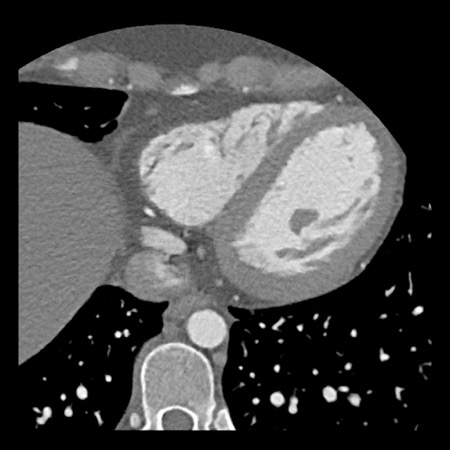

case 4 – CAD-RADS 3/P1/I+ thrombus left ventricle

First, scroll through the CTA images.

How would you describe the findings on the coronary CTA?

The findings are:

- Moderate (50-69%)

stenosis in the proximal LAD caused by a non-calcified plaque. - Variant of

sinoatrial (SA) nodal artery. The artery usually arises from the RCA as a second

branch after the conus artery, however in this case it arises from the LCX,

courses behind the aorta, anastomosing with the right atrium and with a small

branch supplies the SA-node of the heart. - Thrombus in the

apex of the left ventricle. - CTP was performed

in this patient. CTP showed a perfusion defect at stress imaging in the

territory of the LAD (I+), at rest no perfusion defect was visible.

This patient classifies as CAD-RADS 3/P1/I+, which means

this patient requires further investigation.